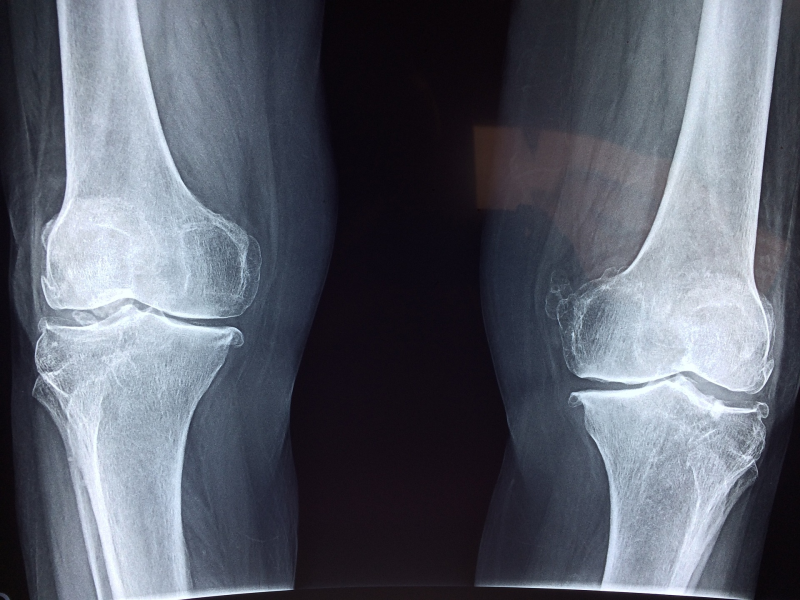

正常來說,關節和關節之間,有軟骨作為緩衝,活動行走時保護關節免於受傷,隨著年紀漸長、或外力因素,這一層軟骨磨損變薄,關節和關節之間空隙變小,「硬碰硬」摩擦、喀拉作響、產生疼痛,就稱為退化性關節炎。

退化性關節炎是中老年人普遍的疾病,最常見的是膝關節退化,其次是髖關節退化,長輩會經常感到關節腫脹、疼痛、僵硬,因而不想走路,身體機能跟著變差,造成惡性循環。